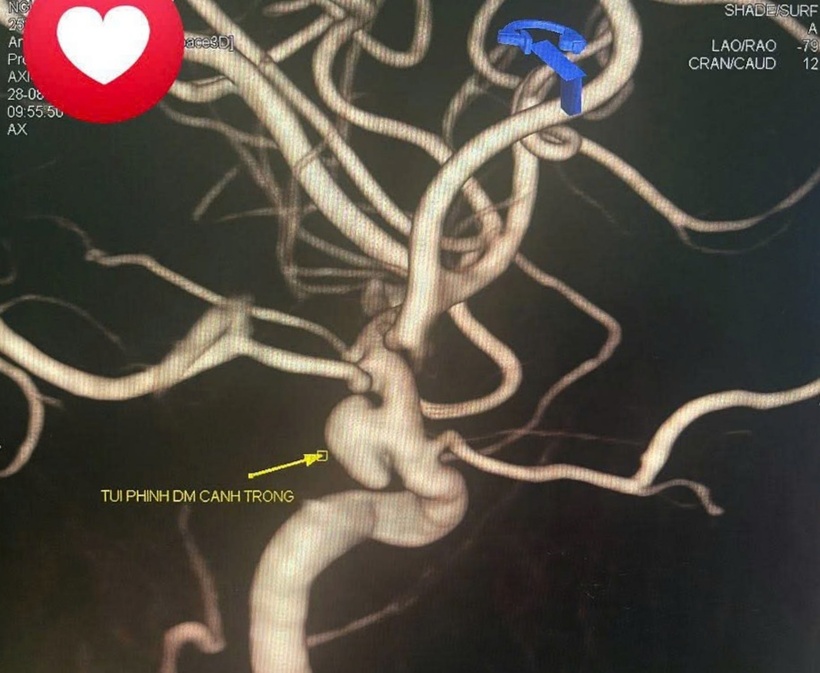

Hình ảnh túi phình động mạch cảnh. Ảnh: Vnexpress.

Theo Vnexpress, ngày 1/9, đại diện Bệnh viện Đa khoa Quảng Ninh cho biết túi phình động mạch cảnh trong trái, kích thước lớn, không có máu tụ quanh song có thể vỡ bất cứ lúc nào, gây đột quỵ xuất huyết não, ảnh hưởng tính mạng. Êkíp sử dụng phương pháp nút túi phình bằng vòng xoắn kim loại (coil) kết hợp stent chẹn cổ túi phình.

Bác sĩ Ngô Quang Chức, Trưởng khoa Chẩn đoán hình ảnh, đánh giá đây là ca khá phức tạp do túi phình có phần cổ rộng, khi nút coil thường khó kiểm soát, có thể trôi vào lòng mạch và gây biến chứng tắc mạch máu não.

Stent đóng vai trò như một giá đỡ tại cổ túi phình, giúp tái lập dòng chảy qua đoạn mạch bị tổn thương, hạn chế các nguy cơ. Quá trình can thiệp đòi hỏi sự chính xác tuyệt đối, từ lựa chọn loại stent và coil phù hợp với đường kính mạch não, thao tác vi ống thông trong lòng mạch vốn rất nhỏ và ngoằn ngoèo. Đặc biệt, bệnh nhân còn trẻ nên mục tiêu điều trị không chỉ là loại bỏ nguy cơ vỡ túi phình tức thì mà còn đảm bảo hiệu quả lâu dài, hạn chế tối đa biến chứng.